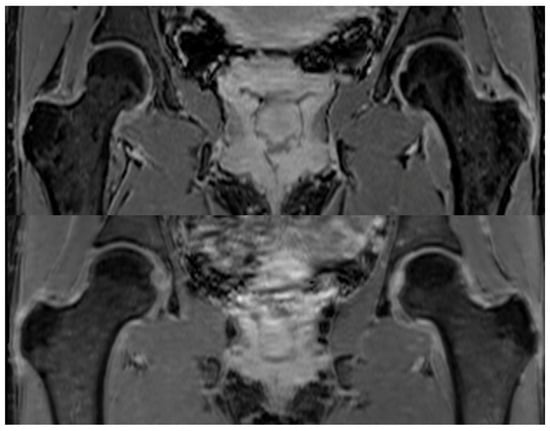

MRI data was obtained from three cohorts (Table 1). Cohorts 1 and 2: These included bilateral hip MRI scans from a total of 41 subjects imaged at a single center. Ethical approval for the study protocol of Cohorts 1 and 2 was obtained from the Institutional Review Board (IRB) before data collection and analysis commenced. Cohort 1 comprised 31 patients with confirmed unilateral FAI (22 females, mean age: 36 ± 8 years), of which 20 scans included contrast-enhanced sequences. All subjects in Cohort 1 were surgically confirmed to exhibit mixed-type FAI (cam + pincer). Cohort 2 consisted of 10 healthy volunteers (5 females, mean age: 32 ± 6 years), scanned without contrast. All MRI exams for these two cohorts were acquired using a consistent imaging protocol: an axial dual-echo T1-weighted three-dimensional (3D) FLASH sequence with Dixon fat–water separation. Acquisition parameters were as follows: repetition time (TR) = 10 ms, echo times (TEs) = 2.4 ms and 3.7 ms, field of view (FOV) = 32 cm, acquisition matrix = 320 × 320, and slice thickness = 1 mm (Figure 1).

Figure 1. Two examples of DIXON MRI sequences highlighting the left and right femurs and the acetabulum of a patient (top) and a healthy subject (bottom). Both images were acquired using an axial dual-echo T1-weighted 3D FLASH sequence with Dixon fat–water separation, enabling detailed visualization of hip joint structures. Although the image contrast appears visually similar between the two cases, the symptomatic patient exhibits a subtle but clinically relevant narrowing of the space between the femoral head and acetabulum. These morphological changes are difficult to appreciate in isolated 2D views, and this challenge underlies the motivation for the current study, which leverages radiomic features to detect and quantify such structural differences objectively.